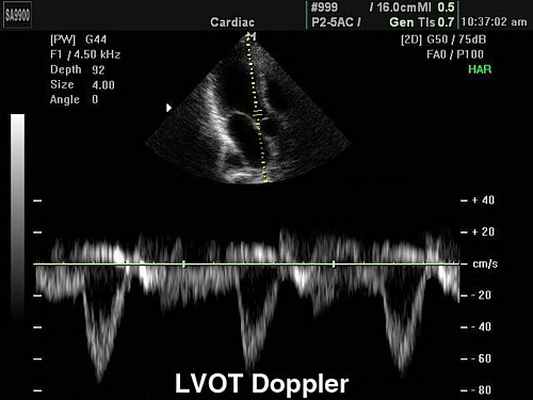

Импульсно-волновая допплерография.

При импульсном режиме, в противоположность непрерывноволновому допплерографическому исследованию, из-за ограниченной возможной частоты повторения импульсов снижается разрешающая способность метода, не позволяющего однозначно идентифицировать скорости потока крови выше определенного порогового значения (скорость Найквиста, или порог искажения, aliasing).

б) Феномен искажения (aliasing). При превышении скорости Найквиста числовые значения спектра скоростей отображаются на другом отрезке шкалы скоростей. Из-за этого феномена, например, невозможно при помощи импульсно-волнового допплеровского исследования измерить чрезвычайно высокую скорость трансаортального потока крови при аортальном стенозе, хотя это возможно в режиме непрерывной допплер-ЭхоКГ. С другой стороны, импульсноволновой режим позволяет измерить скорость движения крови в выносящем тракте левого желудочка даже в том случае, если имеется аортальный стеноз, тогда как при непрерывно-волновой допплерографии более низкие скорости в выносящем тракте будут перекрываться более высокими скоростями на уровне стеноза.

В противоположность непрерывной допплерографии хорошие импульсно-волновые допплеровские спектры обычно не «заполнены» целиком, так как в области контрольного объема регистрируются сходные значения скорости. При этом соотношение сигнал-шум тем лучше, чем больше размер контрольного объема. В результате интегрирования скорости по времени, например интегрирования трансаортальной скорости за время систолы, получают интеграл линейной скорости потока крови (VTI ), который измеряется в сантиметрах или метрах. Умножение этой величины на площадь поперечного сечения аорты позволяет рассчитать ударный объем левого желудочка.

PW – режим импульсно-волнового допплера

Режим импульсно волнового допплера (pulse wave Dopper – PW) – режим, работая в котором мы пытаемся избавится от главного недостатка режима CW, а именно отсутствия пространственного разрешения (разрешающей способности по глубине). Импульсные сигналы (короткие по времени) позволяют оценить отдельные зоны по глубине, поэтому в процессе работы на ультразвуковом приборе нам необходимо выбрать зону интереса (окно опроса). Конечно же и здесь не обошлось без недостатков – главным недостатком использования режима импульсно-волнового допплера является строгое ограничение по измерению больших скоростей на больших глубинах сканирования.